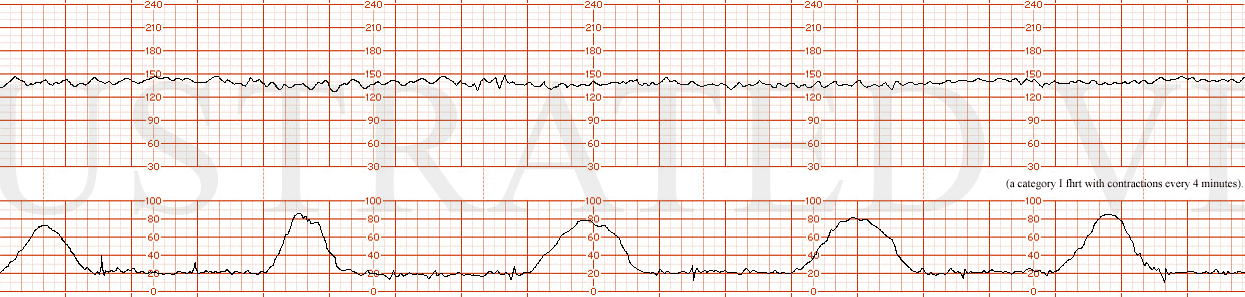

STRIP 99

1. exam now of 9/+1/100%/LOP and after conservative interventions. the accelerations have disappeared, the baseline is unchanged and recurrent variable decelerations developed initially with a nadir of 120 bpm but now the nadir is 95 bpm. The varibility has progressively decreased from moderate to now absent. The contractions are every 4-5 min.